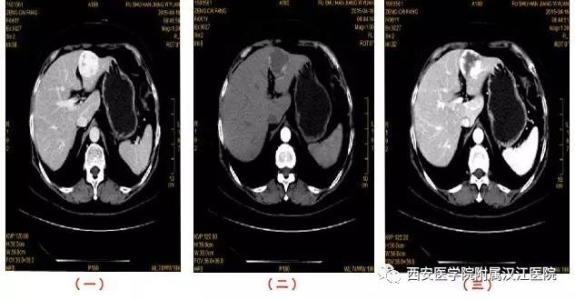

肝脏增强扫描如何鉴别肝癌和肝血管瘤肝癌的影像学特点是平扫描密度低,增强扫描“快进快出”。肝血管瘤的特点是平面扫描密度低,增强扫描造影剂“快进慢出”。造影剂从肿瘤外围逐渐填充肿瘤中心。

摘要:目的探讨肝血管瘤的平片和增强扫描的影像学表现。方法回顾性分析2016年3月至2018年3月经手术、穿刺病理或磁共振核素扫描确诊的42例肝血管瘤的平片和增强扫描图像。结果42例患者的CT大多显示肝脏单发、多发圆形或椭圆形低密度影。增强扫描后,38例表现为典型的肝血管瘤,即动脉期边缘结节状和环状增强特征,延迟期增强区向中心充盈增强。2例病变在动脉期强化,延迟期等密度。2例早期病灶中心明显强化。门静脉和延迟期逐渐充满周围,直至整个病变增强。30例肝脏局灶性结节性增生密度相等或低。动脉期快速、均匀、明显增强;8例原发性肝癌平面扫描显示低密度病灶,增强扫描显示“快进快出”特征。肝脏腺瘤4例,平片显示密度稍低,边界清晰。增强扫描显示动脉期明显增强,门脉期等密度。结论肝血管瘤的平片和增强扫描有很大区别,平片和增强扫描相结合更有利于肝血管瘤的发现。

增强扫描后,动脉期有明显的边缘增强特征,延迟期有充盈变化。早期病灶边缘强化38例,早期完全强化2例,均为局灶性结节增生30例,密度等或低,动脉期强化迅速、均匀、明显。原发性肝癌8例,平片扫描低密度病灶,增强扫描具有“快进快出”的特点。肝脏腺瘤4例,平片显示密度稍低,边界清晰。增强扫描显示动脉期明显增强,门脉期等密度。当充分延迟时,所有病例显示与肝实质的密度大致相等或稍高。

目前,超声诊断主要用于肝血管瘤的临床诊断,包括混合型、低回声型和高回声型[4]。高回声临床诊断具有较高的检出率和突出的诊断价值[5]。但是混合型和低回声型的诊断效果不够理想,影响了患者疾病的早期诊断和鉴别。为了进一步明确诊断,对肝脏进行多期增强扫描具有重要意义,可以准确诊断超声难以诊断的肝血管瘤。在肝血管瘤的CT检查中,大多数病变具有典型的明显的慢进慢出特征,[6]。在后期,造影剂逐渐填充到病变中,其密度与延迟扫描时肝实质的密度相似,这与肝血管瘤的病理特征相一致。